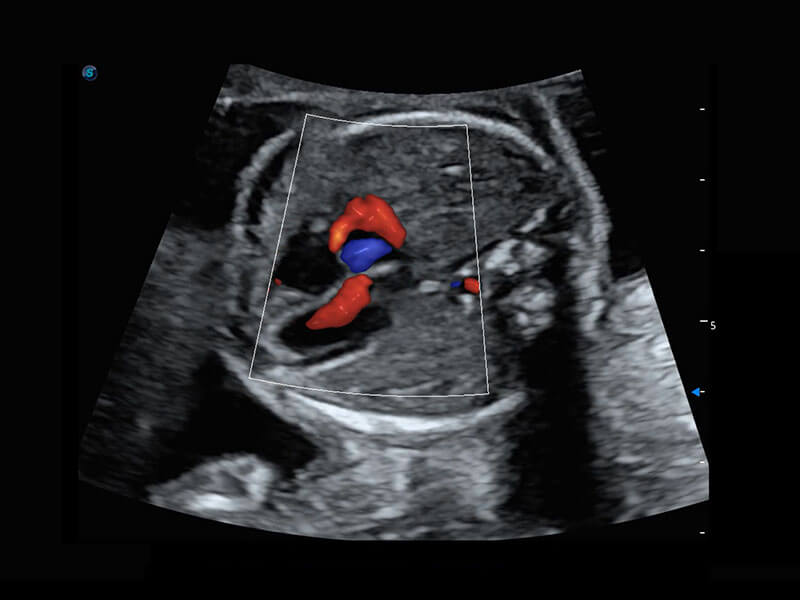

四腔心血流

右室双出口